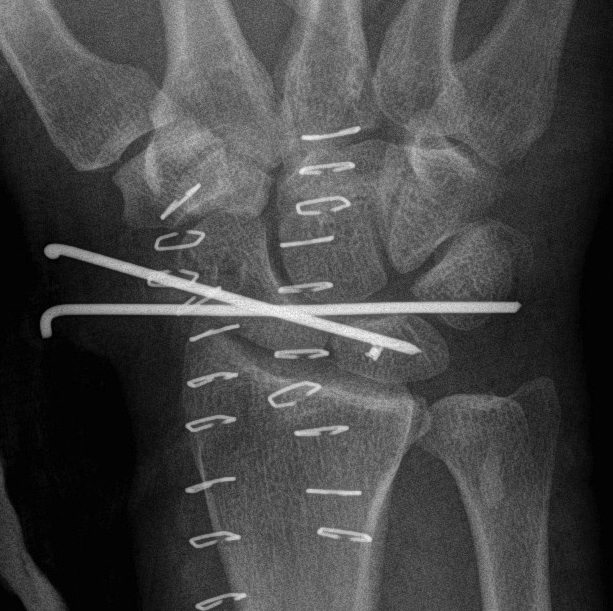

Perilunate fracture-dislocations / Trans-scaphoid perilunate

Dorsal approach

- 3/4 extensor compartment

- mobilise EPL laterally

- capsulotomy: T shaped or Berger (open dorsal between DRC and DIC ligaments)

- ORIF scaphoid fracture with headless compression screws

- assess stability of scapho-capitate and scapholunte joint (often ligaments intact and stable)

- K wires lunate-triquetral +/-

- +/- repair LT ligament

- +/- ORIF capitate

+/- volar approach

- reduce lunate

- carpal tunnel decompression

- repair rent in capsule